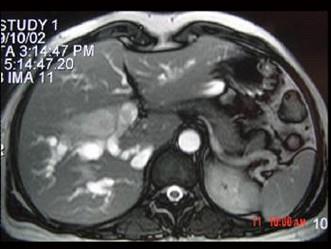

问题 女,35岁,右上腹痛一月,黄疸进行性加重,AFP阴性,消瘦乏力,影像检查如图,最可能的诊断为 ( )

选项 A、原发性肝癌 B、肝血管瘤 C、胆管癌 D、局灶性脂肪肝 E、肝转移癌

答案 C